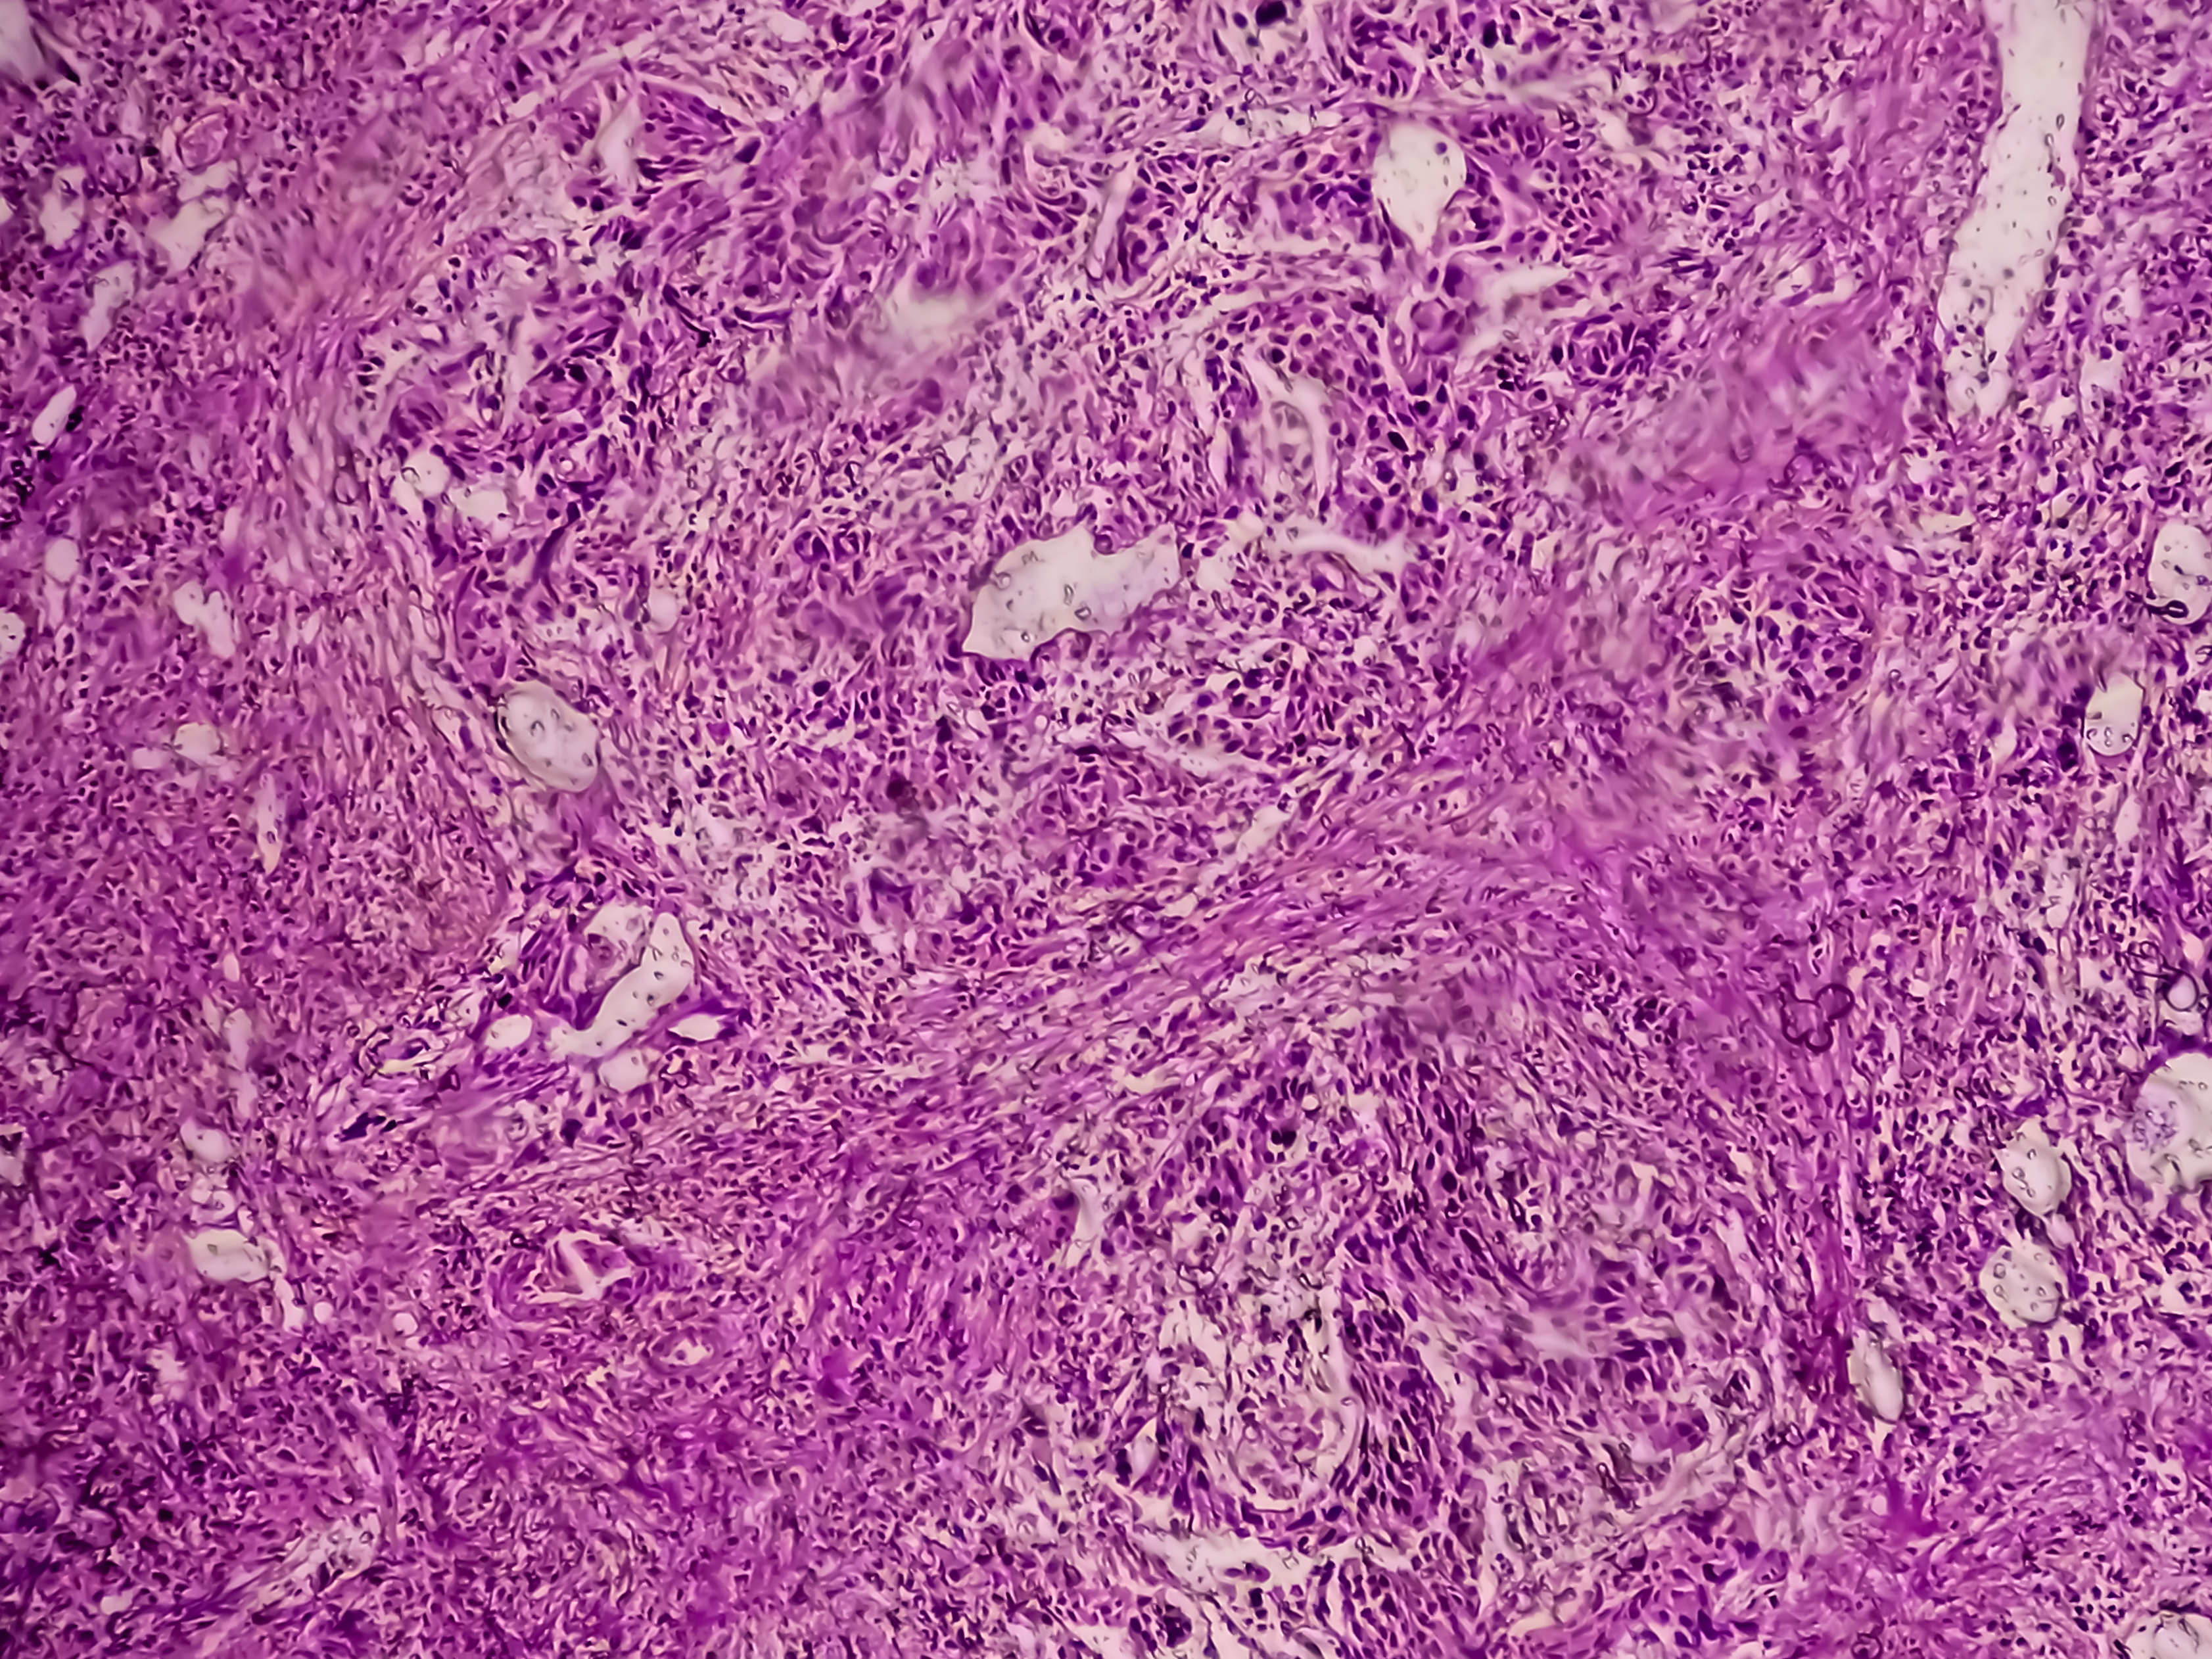

In some cases however, transitional cell carcinoma invades through the lining and into the muscular wall of the bladder, and sometimes into additional nearby organs.

Less common cancers of the bladder include squamous cell carcinomas, which are most common in developing countries. Another is adenocarcinoma, which is a cancer of the cells in the lining of the bladder that produce mucus.